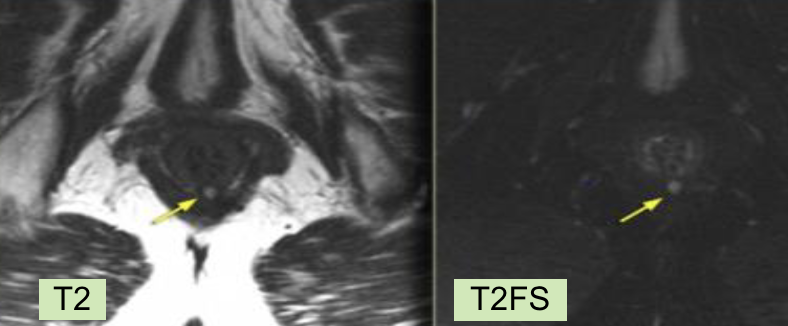

- Hyper T2/Flair (montre bien le trajet fistuleux)

Exemple: Fistule intersphincterienne a 6H

Exemple: Fistule trans-sphincterienne à 6h

Exemple: Fistule trans-sphincterienne 11h